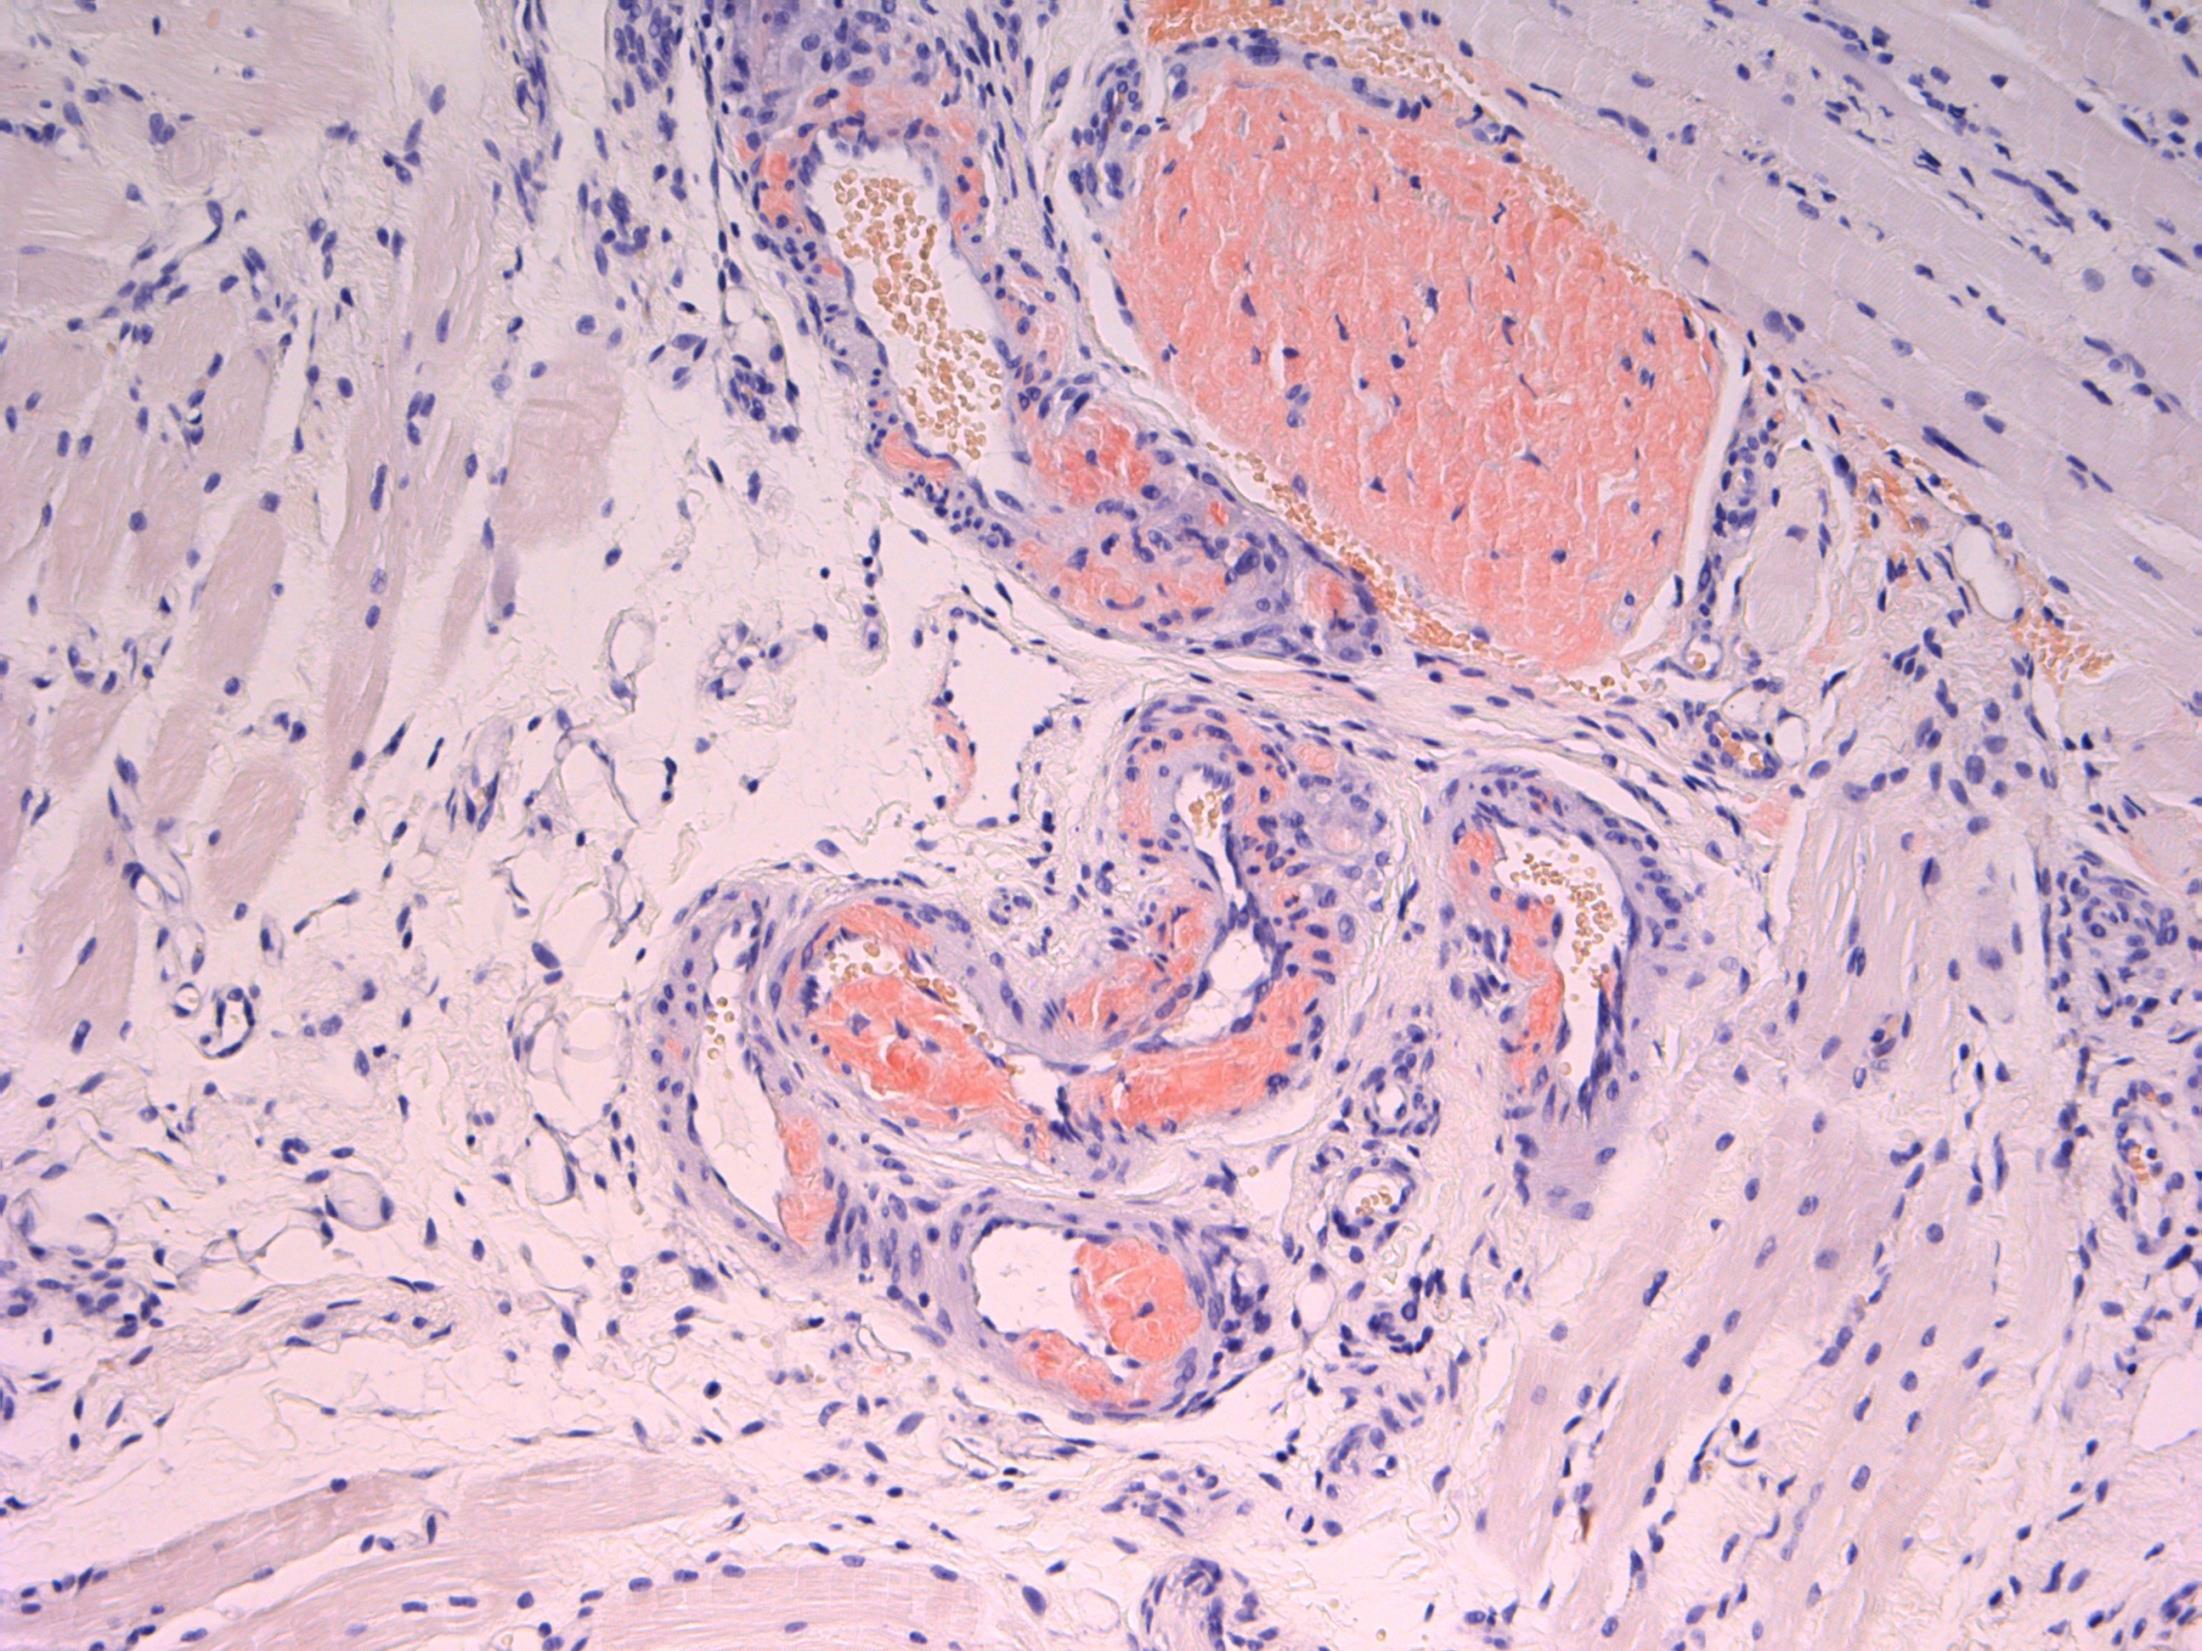

6 • 50M Progressive breathlessness and abnormal liver function tests. Ultrasound shows an abnormal liver texture. Liver biopsy performed.

• Liver biopsy - Cirrhosis with alpha 1 antitrypsin deficiency

Description: Nodules of hepatocytes surrounded by fibrovascular septae. There is ductular reaction and inflammation of varying degrees. Mild steatosis. Also oval cytoplasmic eosinophilic globular inclusions in periportal hepatocytes.

Diagnosis: Cirrhosis with alpha 1 antitrypsin deficiency.

Plan: Liver special stains: A-1 AT – PAS+, diastase resistant, globules in hepatocytes. IHC to A-1AT to confirm.

Correlate with any clinical history of A-1AT lung disease (patient has breathlessness).

Correlate with LFTs, radiology, previous biopsies .

PiZZ genotype. Increased risk of HCC